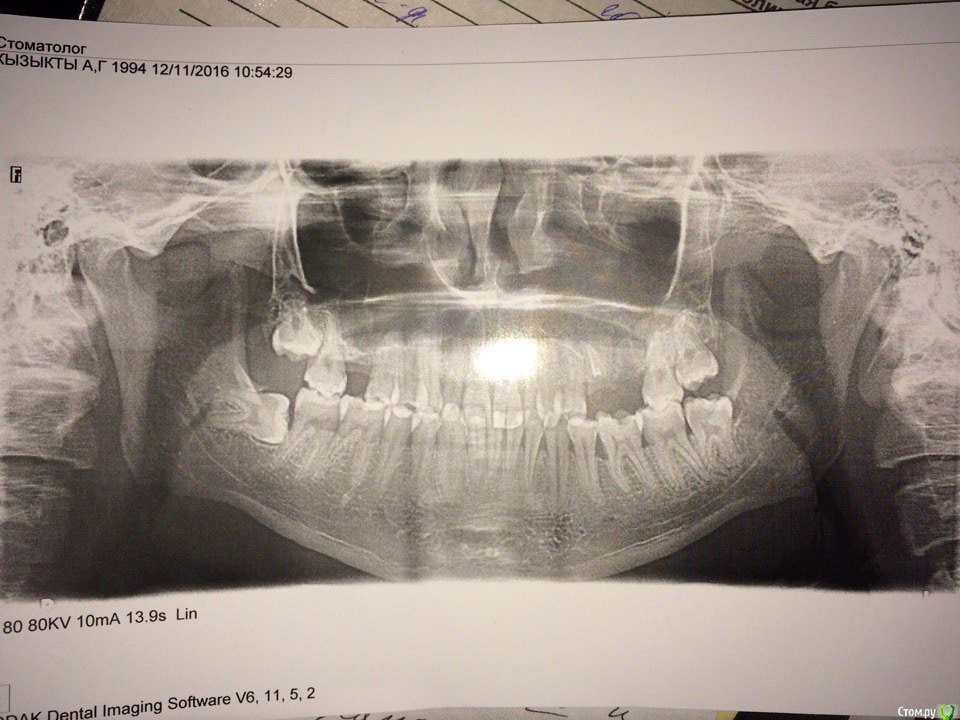

red_butler Опубликовано 30 ноября, 2016 Поделиться Опубликовано 30 ноября, 2016 Делайте Кт с захватом придаточных пазух носа. 1 Ссылка на комментарий

kyzykty1894 Опубликовано 28 декабря, 2016 Автор Поделиться Опубликовано 28 декабря, 2016 Делайте Кт с захватом придаточных пазух носа.Здравствуйте! Я сделал КТ, но никак не могу загрузить сюда Ссылка на комментарий

dok1 Опубликовано 28 декабря, 2016 Поделиться Опубликовано 28 декабря, 2016 Щадящий режим как можно дольше. Слизистая укрепится. Но для имплантации нужна будет костная пластика. Ссылка на комментарий